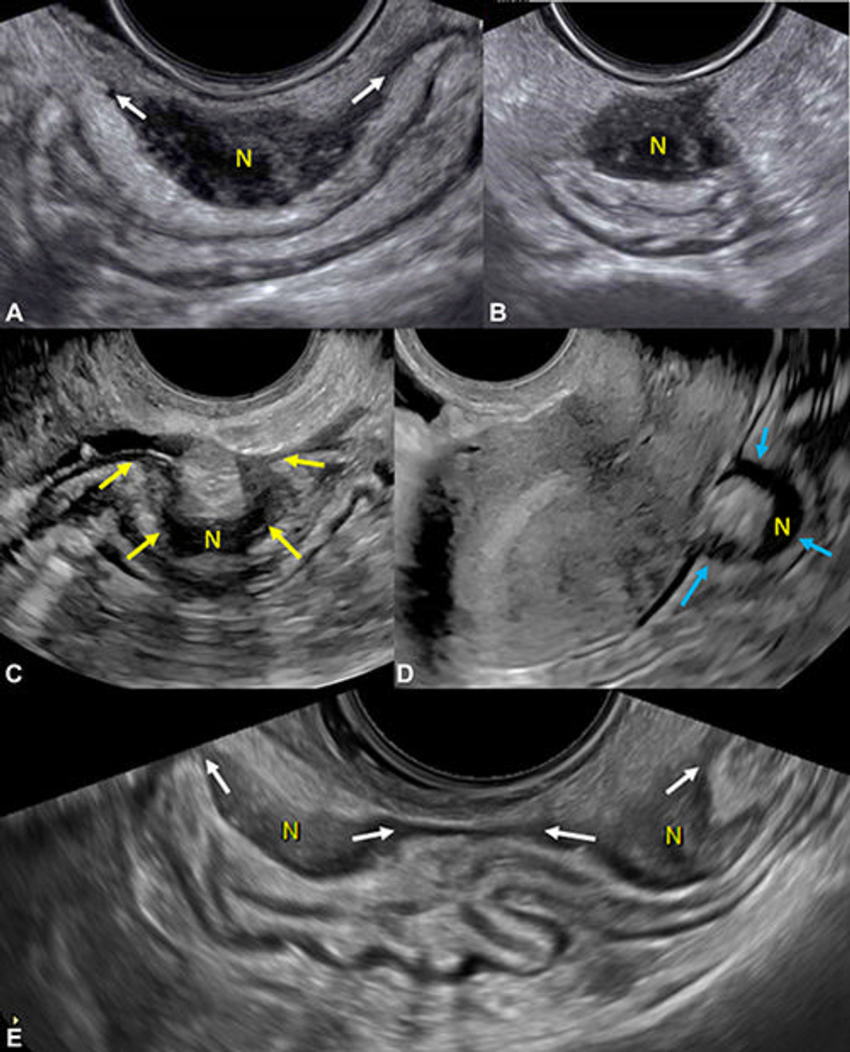

Figure 12. Transvaginal US shows deep endometriosis (DE) nodules (N) in the rectosigmoid colon. (A) Image in a 31-year-old patient with dyschezia shows an elliptical DE with tapering ends (arrows), longitudinal posterior fornix. (B) Transverse image of nodule in A, posterior fornix. (C) Image in a 27-year-old patient with chronic pelvic pain shows an Ω-shaped DE nodule in midrectum, longitudinal posterior fornix (arrows). (D) Image in a 33-year-old patient with deep dyspareunia shows a C-shaped nodule in midrectum, longitudinal anterior fornix (arrows). (E) Image in a 40-year-old patient with chronic pelvic pain shows tandem nodules of rectosigmoid colon with tapering ends (arrows), longitudinal posterior fornix. These are category A (ie, direct endometriosis) observations.